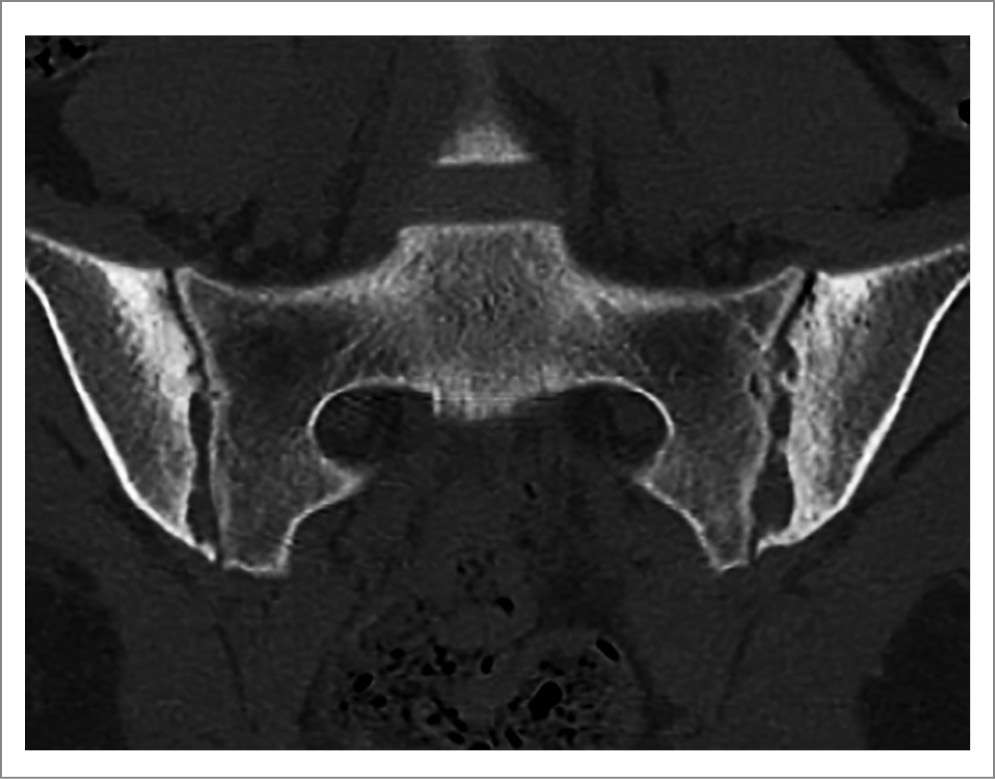

Остеоартроз КПС. Возможность дегенерации КПС следует учитывать уже в четвертом десятилетии жизни. В старшем же возрасте остеоартроз этих суставов по визуализационным данным возникает часто, хотя болевые ощущения в нижней части спины нетипичны. На КТ отмечаются сужение суставной щели (ширина менее 2 мм), субхондральный остеосклероз (обычно неширокий и гомогенный), четко отграниченный от нормальной костной ткани, остеофиты, а иногда вакуум-феномен и субхондральные кисты. Анкилоз не развивается. Изредка описываются мелкие единичные эрозии или неровности суставного края, напоминающие эрозии. Дегенеративные изменения КПС закономерно возникают у пациентов со сколиозом позвоночника и такими аномалиями развития, как переходные крестцово-поясничные позвонки и добавочные КПС. Оптимальным методом обнаружения дегенеративных изменений КПС является КТ (рис. 17). МРТ не позволяет точно измерить ширину щели КПС и выявить небольшие остеофиты, то есть кардинальные признаки остеоартроза. Однако с помощью МРТ можно обнаружить иногда возникающий отек костного мозга. Его особенностями при остеоартрозе КПС являются небольшие размеры, ограниченная глубина (отек виден не более чем на 1–2 срезах) и локализация в передней части сустава по соседству со склерозированными участками, внутри этих зон и/или около остеофитов. Если у пациентов отек костного мозга обнаружен только в передней части КПС, рекомендуется поиск (с помощью КТ) других признаков, указывающих на дегенеративную патологию суставов.

Рис. 17. Остеоартроз КПС у 39-летней пациентки со сколиозом и болями воспалительного типа в области крестца. На КТ отмечаются неровность суставных поверхностей, их локальное сужение (преимущественно слева), двусторонний субхондральный склероз подвздошных костей и краевые остеофиты (слева), эрозий не обнаружено (заимствовано из [22]).